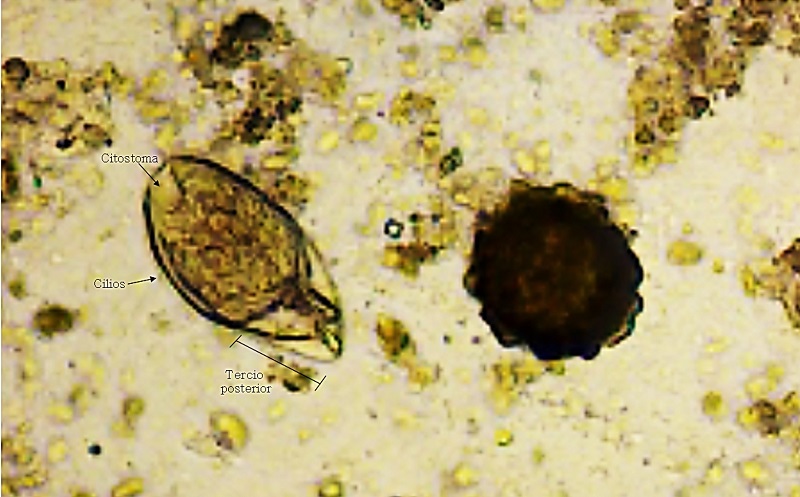

• Balantidium nawaraoi

Balantidium nawaraoi. Rev Pediatr Aten Primaria. Vol. 23. N.º 89. Marzo 2021.